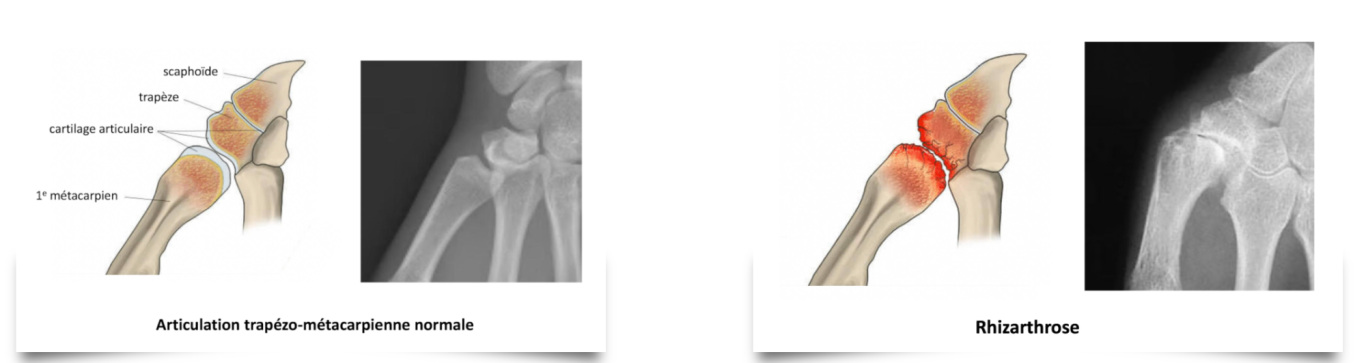

Rhizarthrose

DEFINITION : La rhizarthrose est l’arthrose de la base du pouce. C’est l’usure du cartilage entre le premier métacarpien et un os appelé trapèze. Cette usure progressive est relativement fréquente et touche surtout la femme (1 femme sur 6 après 60 ans). Elle touche souvent les 2 mains. Certaines formes sont héréditaires et peuvent alors apparaître avant la cinquantaine. Il n’y a pas de relations entre l’importance de l’atteinte sur les radios et l’importance de la gêne chez le patient.

EXAMENS : Les radios confirment le diagnostic et permettent au chirurgien d’apprécier l’importance de l’arthrose pour choisir la meilleure technique.